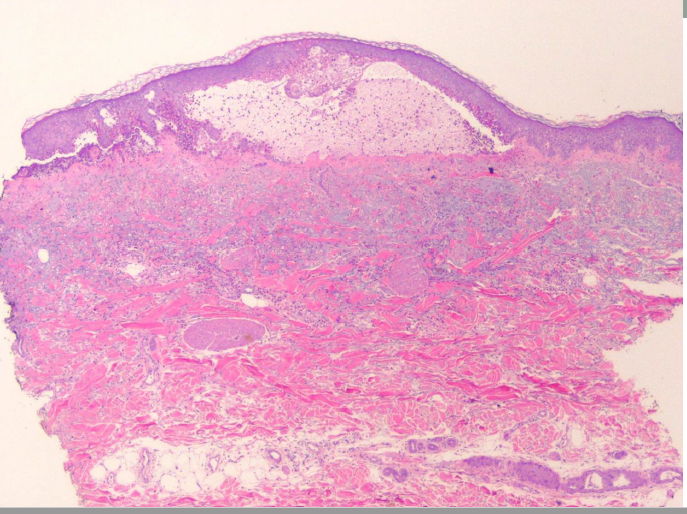

How is BP diagnosed?

Skin biopsy for routine studies and direct immunofluorescence (DIF) studies showing a band of IgG and C3 at the dermal-epidermal junction

Describe the histology of PV

‘row of tombstones’ appearance with intraepidermal split (within epidermis) and signs of acantholysis (individual cells losing attachments)